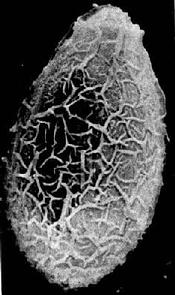

卵在近子宫前端已渐成熟,排出的卵呈黄褐色,内有成熟的毛蚴。卵甚小,平均为29×17µm,形状似芝麻,一端较窄且有盖,盖周围的卵壳增厚、形成肩峰,另一端有小疣状突起(图14-7、14-8)。

华支睾吸虫卵扫描电镜图

图14-8 华支睾吸虫卵扫描电镜图(许世锷供图)